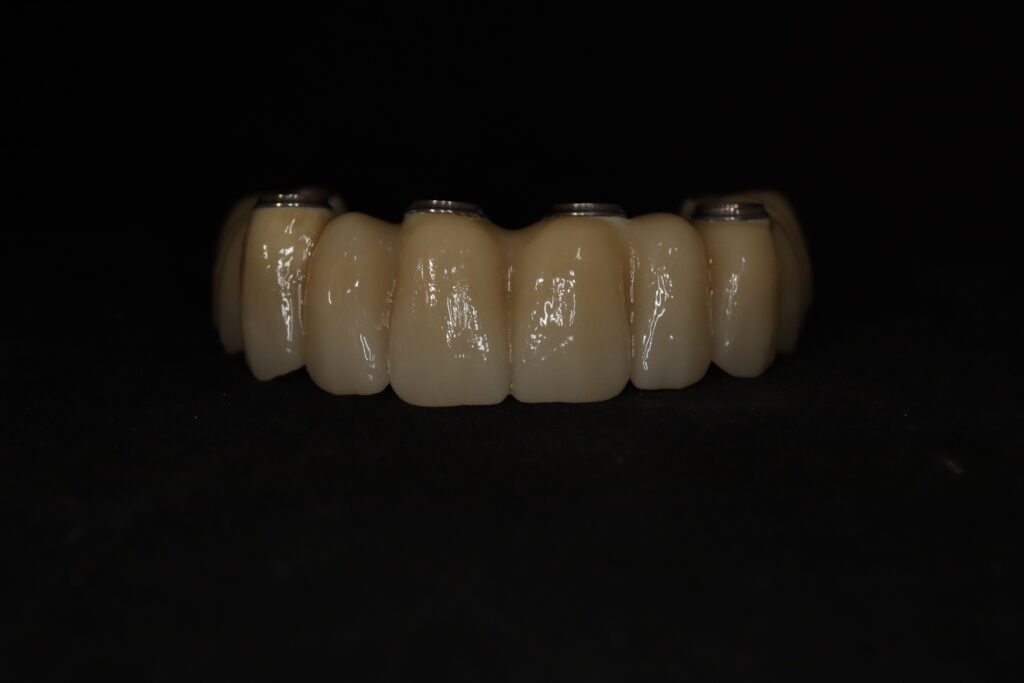

Спустя 20 дней был зафиксирован протез с опопрой на дентальные имплантаты из диоксида циркония.

результат имплантации